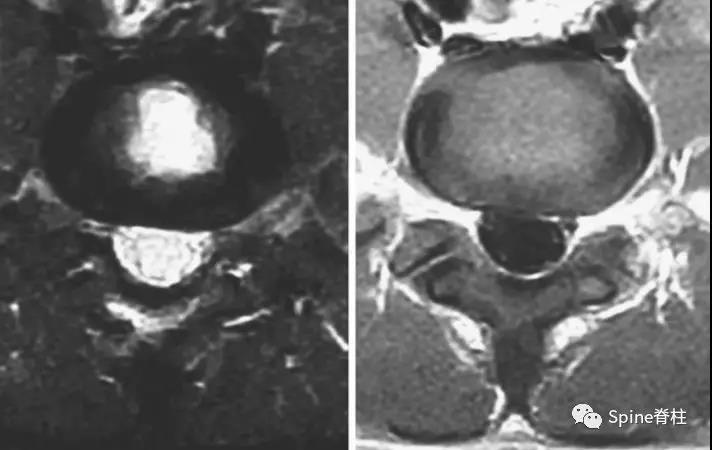

2003年发表在Am J Sports Med杂志(IF=6.20)上的病例报道,很好的阐述了峡部裂和椎弓根裂的变化。描述一个17岁的棒球运动员,运动后腰痛1月余,随访的辅助检查提示相同椎体水平出现的3个连续性应力性骨折:第一次为左侧峡部,第二次为右侧椎弓根,第三次为右侧峡部。

图:起始CT提示L5左侧峡部裂(双箭头),起始CT检查后2个月复查可见出现右侧椎弓根裂(单箭头),4个月复查可见椎弓根裂愈合(单箭头)